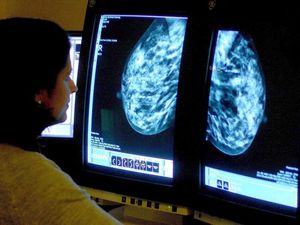

Scientists have discovered a protein which drives aggressive breast cancer.

Their study looked at an aggressive type of breast cancer called triple negative, which is resistant to hormone therapy and occurs in around 15% of cases.